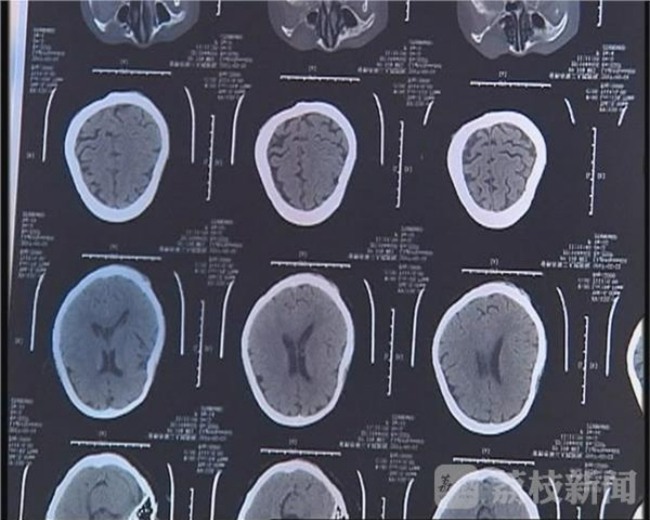

Kết quả là bà Từ phải nhập viện trong trạng thái bị gãy 11 chiếc xương sườn, thủng màng nhĩ tai trái và bị chấn thương ở nhiều vùng trên cơ thể.

Nằm bẹp trên giường bệnh ở bệnh viện Nhân dân Số 2 xã Thường Thục, bà Từ đau đớn kể lại, khi đã đánh mẹ đến mức bất tỉnh nhân sự, đứa con trai bất hiếu còn dùng nước lạnh tạt thẳng vào mặt bà để bà tỉnh lại tiếp tục hứng chịu những cú đánh như trời giáng.